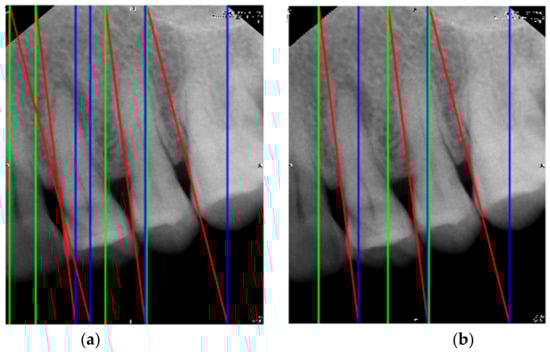

2.1.1. Vertical Cutting

2.1.2. Image Masks